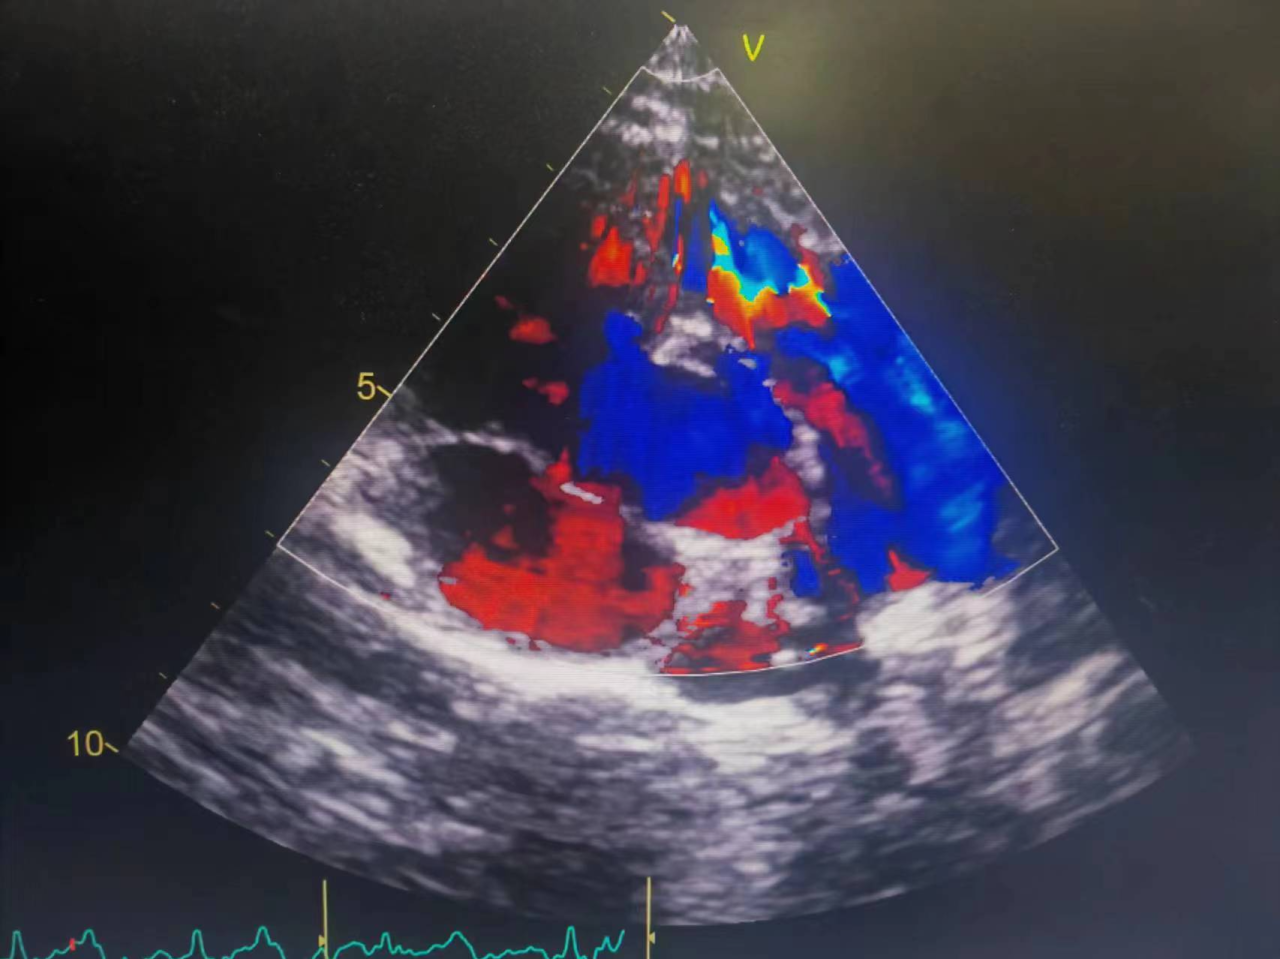

心脏传出“异响”案例 综合检查结果,患者被诊断为风湿性心脏瓣膜病,二尖瓣关闭重度不全、三尖瓣重度关闭不全、心律失常-心房颤动、心功能Ⅲ级。